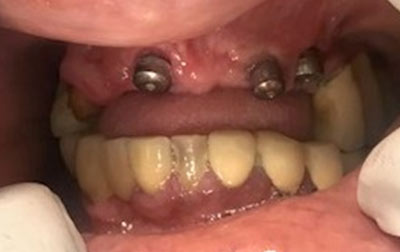

Nobel Implants- Nobel Implant is a breakthrough in dental restoration. Crafted with precision, the Nobel Implant offers a seamless solution for missing teeth, ensuring both functionality and aesthetics. Engineered from biocompatible materials, it seamlessly integrates with your jawbone, providing stability and long-lasting support. Our seasoned specialists meticulously execute the implant procedure, employing state-of-the-art technology for optimal results and minimal discomfort. Experience restored confidence in your smile, improved speech, and enhanced chewing capabilities. Say goodbye to discomfort and slipping dentures. With Nobel Implant, embrace a natural-looking, permanent solution that redefines your dental well-being, one smile at a time.

All-on-four Implants-The All-On-4 dental implant technique revolutionizes tooth replacement by utilizing only four implants to support an entire upper or lower set of teeth. This innovative approach involves strategically angling the posterior implants at a 45° tilt towards the back of the mouth. These implants are then precisely positioned within the front part of the upper jaw (anterior maxilla), a region known for its denser bone structure. What sets the All-On-4 method apart is its ability to provide stable implant support even in cases where bone density might otherwise be insufficient for traditional implant procedures.